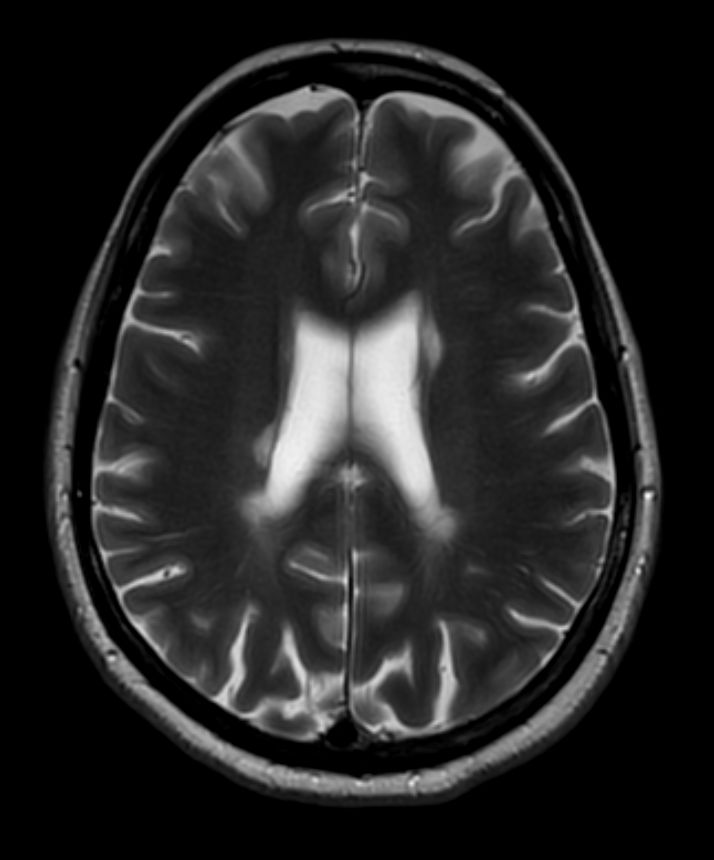

T2w TSE MultiVane XD